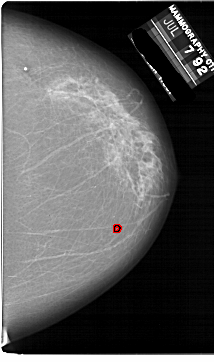

A_1861_1.LEFT_MLO

LEFT_MLO LINES 6136 PIXELS_PER_LINE 4726 BITS_PER_PIXEL 12 RESOLUTION 43.5 NON_OVERLAY

FILE: A_1861_1.RIGHT_MLO.OVERLAY

TOTAL_ABNORMALITIES 1

ABNORMALITY 1

LESION_TYPE CALCIFICATION TYPE PLEOMORPHIC DISTRIBUTION CLUSTERED

ASSESSMENT 4

SUBTLETY 2

PATHOLOGY BENIGN

TOTAL_OUTLINES 1

BOUNDARY